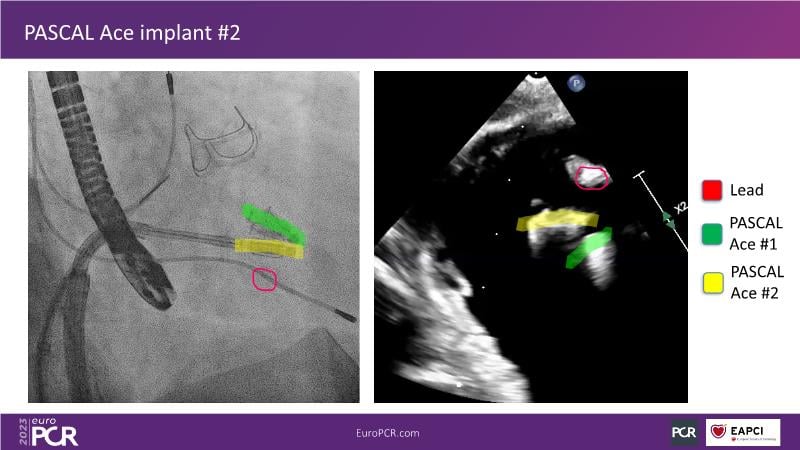

Tailoring tricuspid regurgitation patient treatment with the PASCAL Precision system

Watch this session to discuss exciting cases of tricuspid regurgitation, learn about the proposed new integrated classification for tricuspid regurgitation and enjoy a live presentation of the PASCAL Precision Repair System using a beating heart simulator, among others!

- To discuss the different tricuspid regurgitation phenotypes that can be treated with the PASCAL Precision repair system

- To participate in a case-based discussion using the PASCAL Precision repair system for the treatment of tricuspid regurgitation